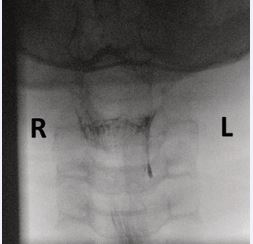

An 11-year-old boy presented with a tender swelling on the left side of the neck at the level of the thyroid. Magnetic resonance imaging (MRI) demonstrated a small effusion within the thyroid gland and an abnormality in the left pyriform sinus. A subsequent barium swallow showed a contrast-filled tract extending 1.6 cm from the apex of the left pyriform sinus (Figure 4). Flexible endoscopy confirmed the internal opening, which was successfully cauterized under general anesthesia.

Figure 4 Barium swallow revealing a contrast-filled tract extending from the apex of the left pyriform sinus.